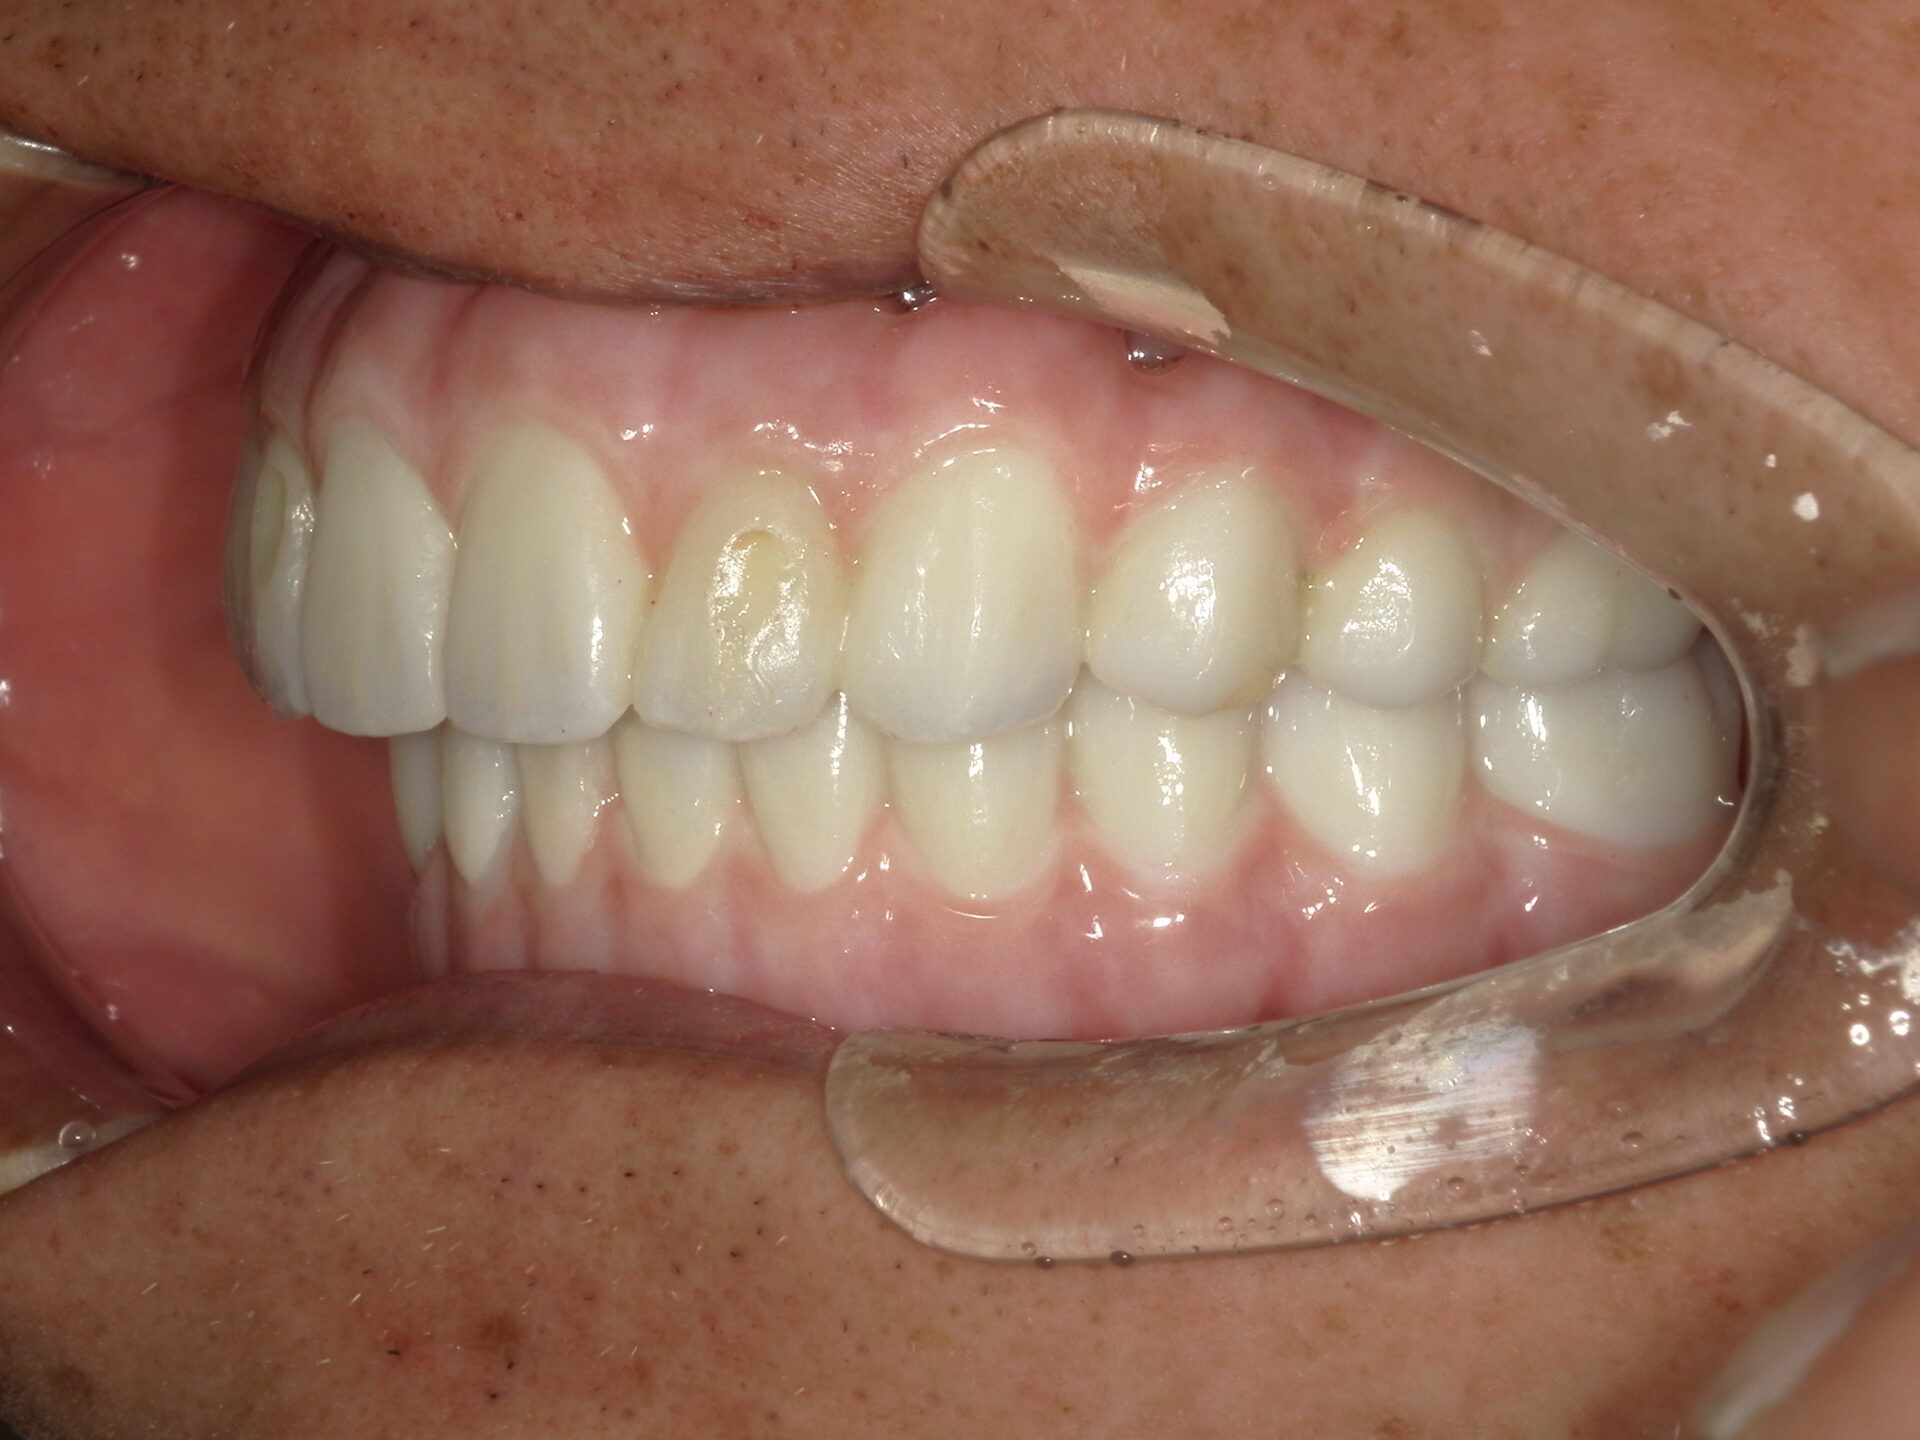

before

after

患者さんの年齢 50代 男性 症状 何も噛めない 治療内容 インプラント治療(オールオン4) 費用 費用900万(税抜) 治療期間・回数 治療期間2年・通院回数12回 メリット なんでも噛めるようになる 見た目が綺麗 デメリット・リスク 骨造成などで費用が増える場合がある - インプラント治療